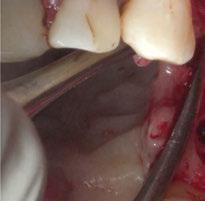

Para ilustrar el proceso, presentamos el caso de una mujer joven diagnosticada de carcinoma adenoide quístico en la región posterior del hemipaladar izquierdo (Figuras 1 y 2). El procedimiento quirúrgico realizado fue una

maxilectomía parcial que incluyó las piezas 24-26 y desde el reborde alveolar hasta la base del cráneo (Figuras 3 y 4). En este caso, la órbita y el globo ocular pudieron ser preservados. La reconstrucción inmediata se realizó mediante un colgajo de músculo temporal homolateral (Figura 5) y el defecto de la fosa temporal fue cubierto mediante una malla de titanio. Posteriormente, la paciente recibió radioterapia (Figuras 6 y 7). 2 años más tarde se diseñó un IS con anclaje en el arbotante nasomaxilar, zona subnasal izquierda

Figura 3. Maxilectomía parcial.

Figura 4. Defecto maxilar tras resección del tumor.

y lo que se pudo preservar del hueso malar. Se añadió una malla sinterizada infraorbitaria para dar volumen a la mejilla y se planificaron dos brazos de conexión que emergieran en las posiciones 24 y 26 de forma subgingival (Figuras 8 y 9). La superficie interna que apoyaba en el hueso era de titanio microrrugoso, y la superficie externa y conectores de titanio pulido y hexágono externo universal (Figuras 10 y 11). La cirugía se hizo bajo anestesia general en infiltración con anestesia local (4% articaína, 1:100.00 epinefrina), levantando el

colgajo cutáneo de la mejilla por vía intraoral, preservando el colgajo temporal para no comunicar con el remanente de la cavidad naso maxilar (Figura 12). Se emplearon 10 tornillos de osteosíntesis de 1,9 mm y la estabilidad primaria obtenida fue excelente (Figura 13)